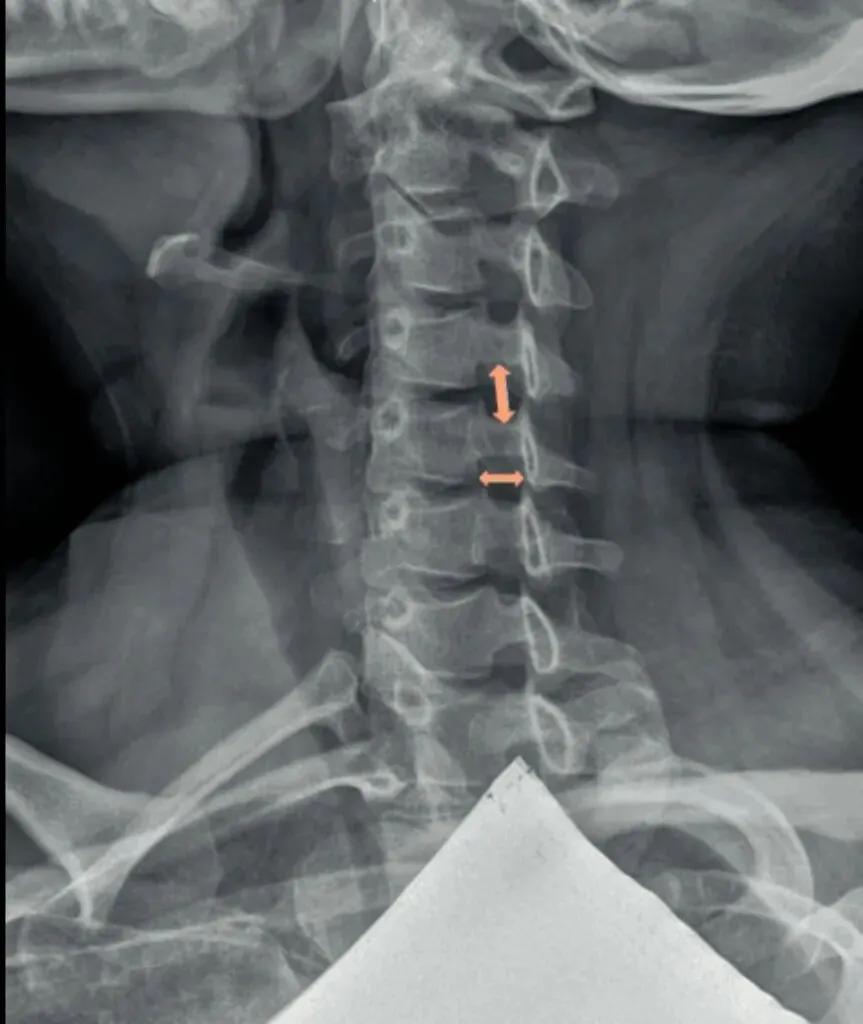

六旋指颈椎旋转,需结合颈椎正侧位观察。

颈椎正位主要观察棘突有没有偏歪,有没有在棘突中心轴线的连线上。

如果某一节椎骨的棘突中心点偏离,各棘突中心连线大于等于3毫米,则表示该节段颈椎有轴向旋转。

侧位主要观察椎体有没有双边征和关节突有没有双突征。

造成这两个征象的原因就是椎体后缘及双侧关节突没有完全重叠,摄影体位不标准时也会出现这种现象。所以我们要结合正侧位观察,如果正位没有出现某节段颈椎棘突偏移,但是侧位出现颈椎双凸或双边征时,大概率就是摄影体位不标准。反之正位能看到某节段颈椎棘突偏移,同时侧位能看到对应节段颈椎的双边或者双凸征时,基本可以确定椎体存在旋转。